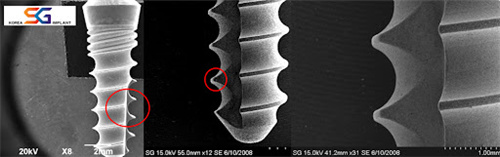

韩国SG种植体局部放大

韩国SG种植体与登腾、奥齿泰同属韩系中高端阵营,但价格更亲民。其材质采用四级纯钛或钛合金,生物相容性优异,能减少排异反应风险,稳定性对标一线品牌。

不同于低价植体牺牲品质的做法,SG通过优化生产工艺降低成本。例如表面采用喷砂酸蚀或纳米涂层技术,增加骨结合面积,加速愈合。这种“减价不减配”策略,让它成为中端市场的口碑之选。